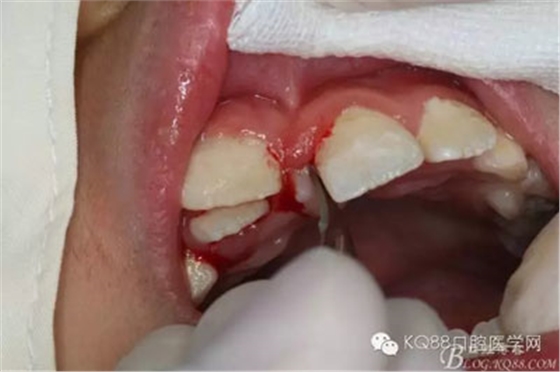

圖7.在11與21之間的牙槽嵴頂做直線切口,并延伸至11與21的腭側(cè),不做附加的松弛切口。

圖8.翻開腭側(cè)粘骨膜瓣,多生牙被骨質(zhì)完全覆蓋